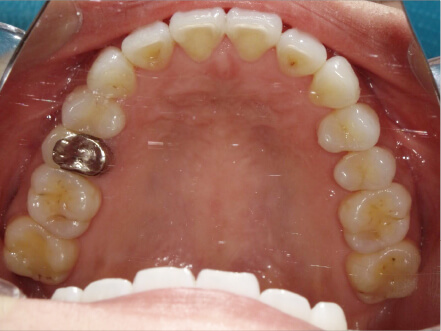

叢生の症例

10歳

/

女性

相談内容

スペース不足

カウンセリング・診断結果

myoからの移行。スペース不足のためインビザライン開始。

治療内容・方法

全額アライナー矯正

術後の経過・現在の様子

クリアライナー使用

治療のリスク

痛み・歯根吸収・歯肉退縮・虫歯・後戻り

費用・治療期間

(インビザのみ)385,000円、1年2ヶ月 + myo3年4ヶ月

トレーニングなど